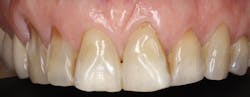

Figure 5: Erosion pattern suggests lemon sucking.

Tooth wear is a process resulting from three primary factors-abrasion (from the interaction of teeth with other materials); attrition (from tooth-to-tooth contact); and erosion (wear after teeth come into contact with environmental or dietary acids) (see Figures 2-5). In addition, numerous behaviors and health factors contribute to the process of tooth wear, including, but not limited to: a diet high in acidic beverages and foods, bruxism, aggressive or improper tooth brushing, low pH of the oral cavity (acid reflux, GI disorders, bulimia nervosa) and oral hygiene habits.

Another important step to help patients reduce tooth wear is evaluating dietary habits, overall health, and lifestyle behaviors. Factors that increase the risk of tooth wear include a diet rich in acidic foods and beverages (citrus fruits and red wine, for example), gastroesophageal reflux disorder, and/or bruxism. Toothpaste containing stabilized stannous fluoride (Crest Pro-Health, for example) has been shown to be significantly more protective than other types of fluoride dentifrices against dental erosion, a factor in tooth wear.11,12